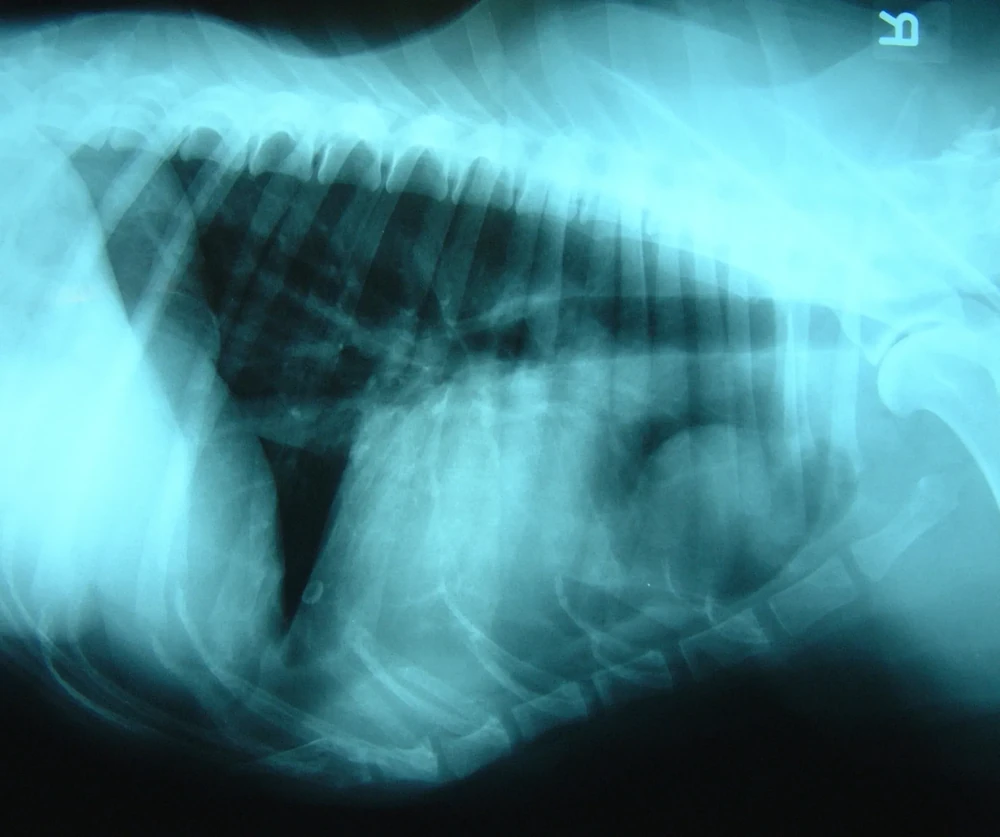

Diagnosis usually happens in layers. A vet will start with a physical exam and history, then move to imaging. Chest X-rays are often the first step, and they can show lung masses, changes in lung pattern, and sometimes enlarged lymph nodes.1, 7

A CT scan can provide a much clearer map of what is happening in the chest, including the size and location of a mass, whether lymph nodes look involved, and whether there are multiple lesions that might suggest spread.1, 7